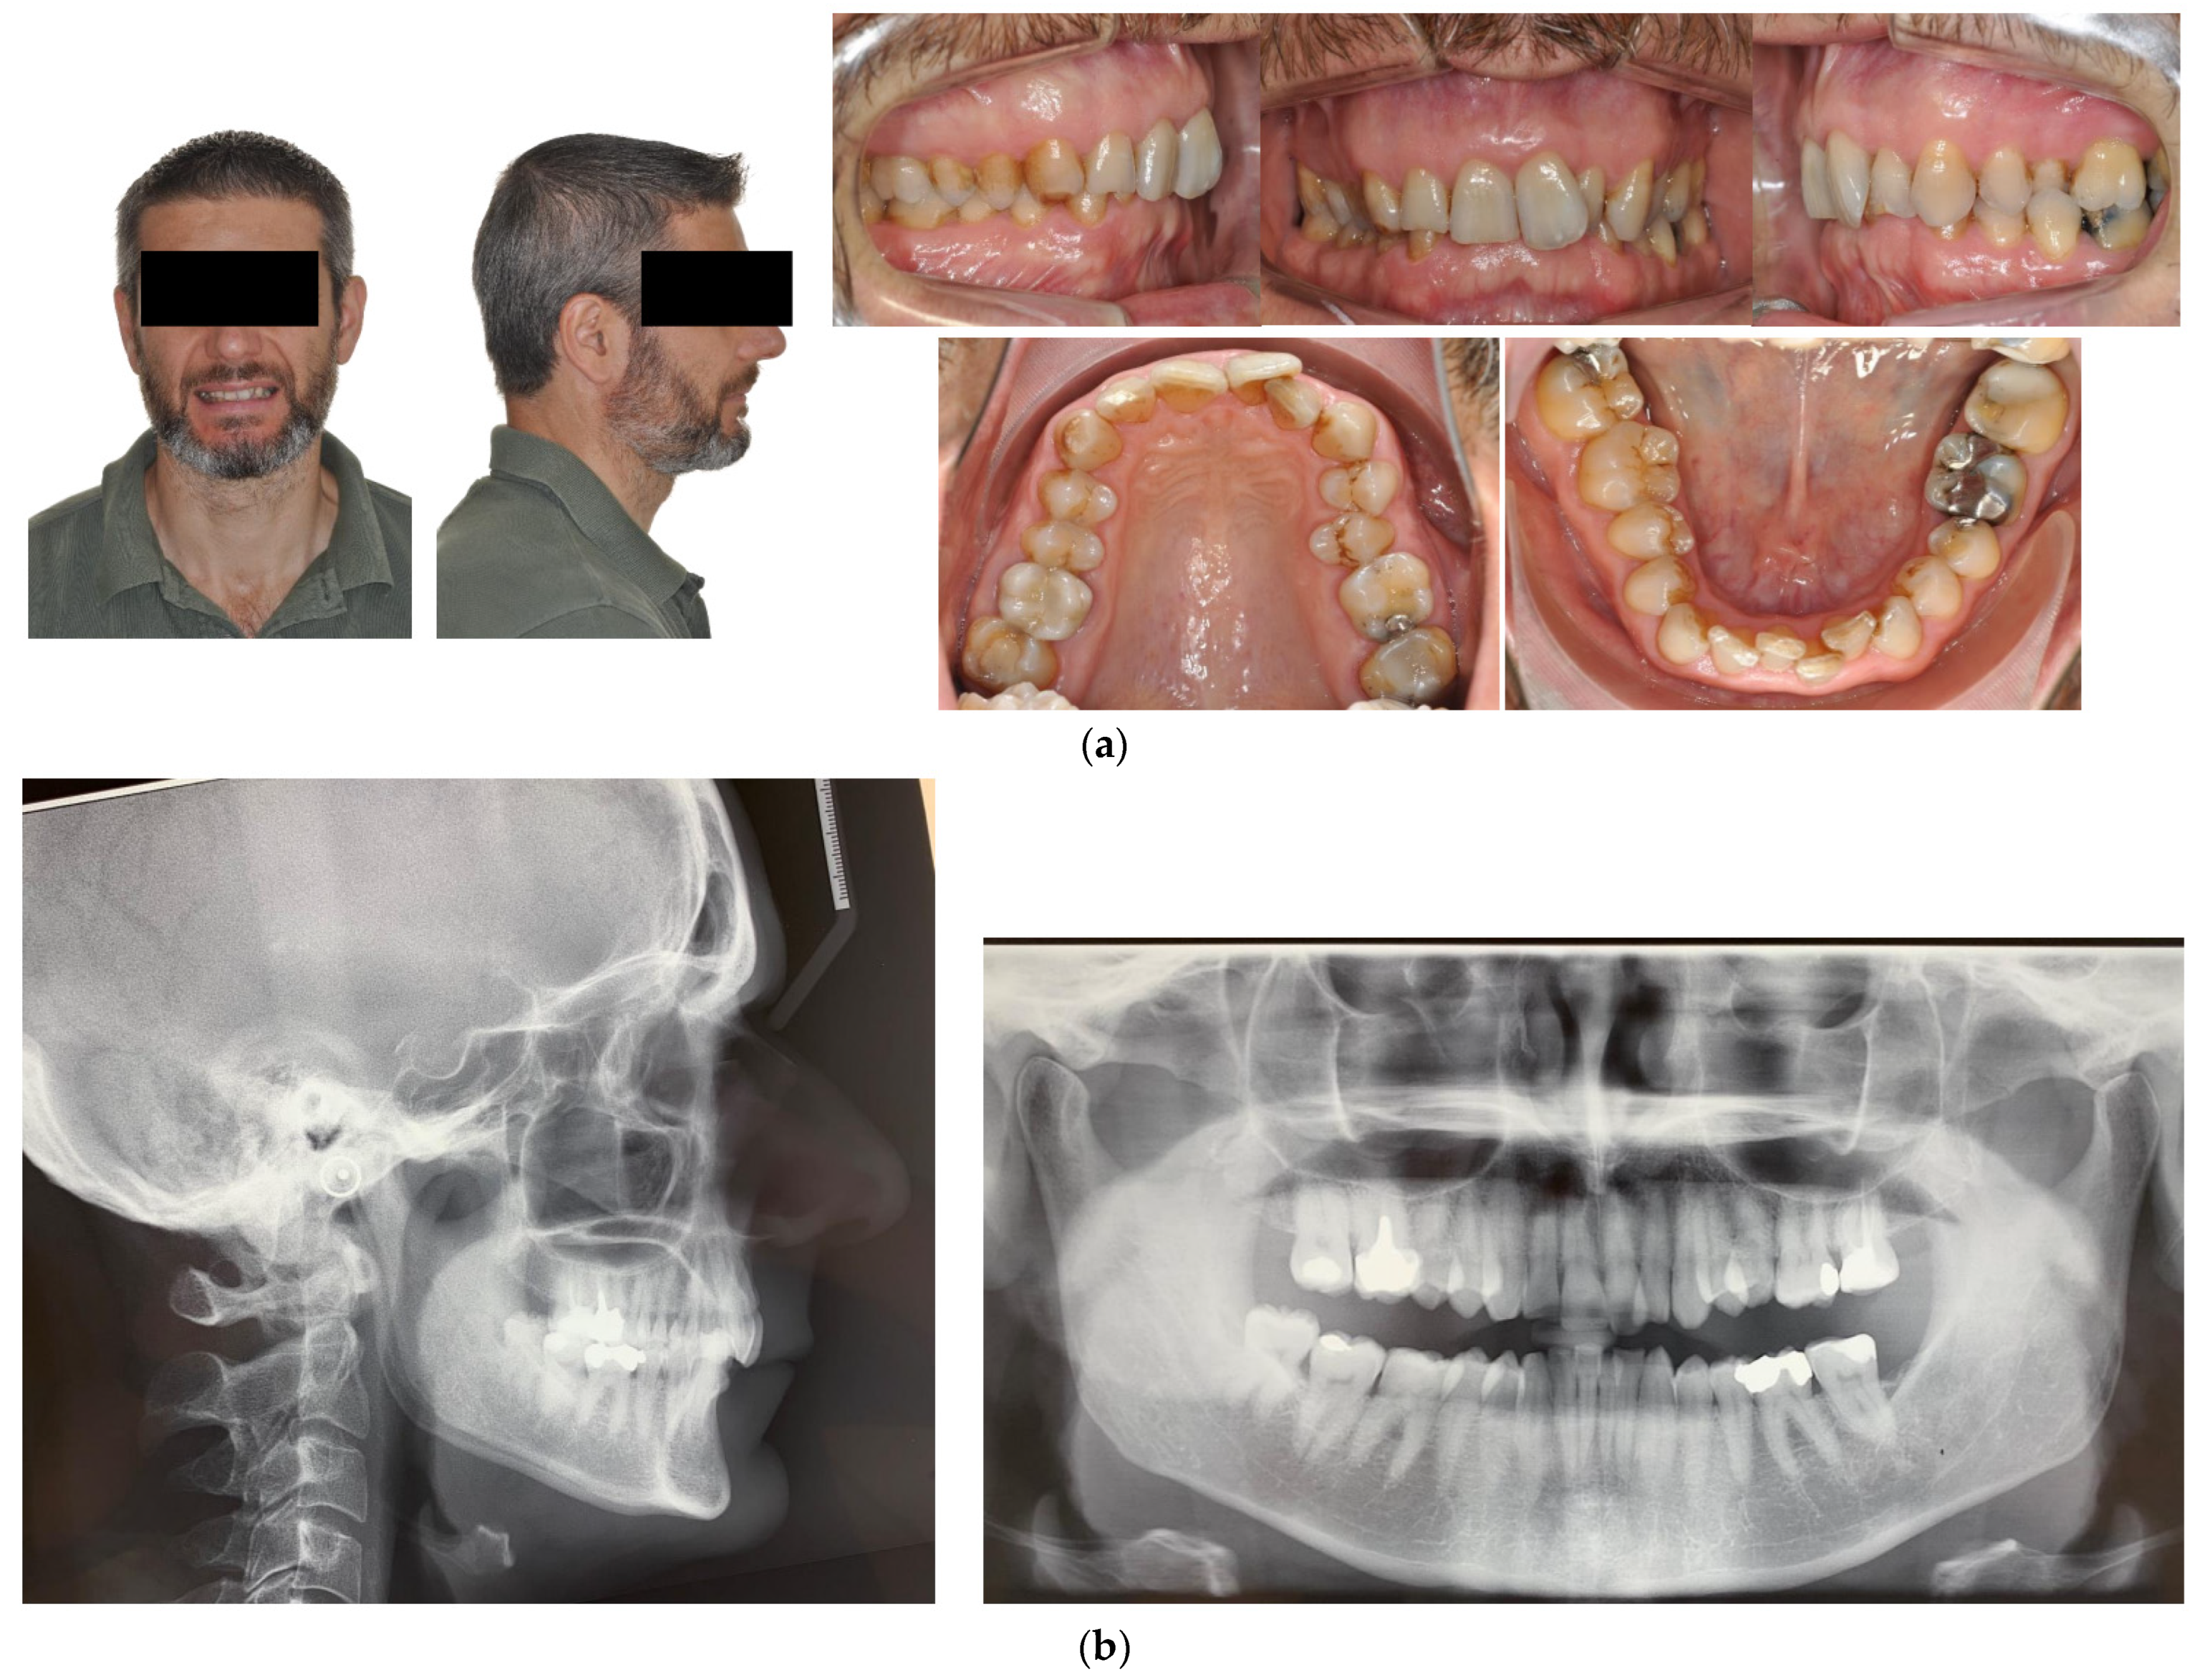

The patient was a 50-year-old male seeking orthodontic treatment for aesthetic reasons. His teeth were crowded, and he presented a concave profile with reduced lower facial height. An intraoral exam revealed a class II division 2 occlusal relationship and a severe deep bite in a hypodivergent facial type. There was severe crowding in both arches. The upper arch was narrow and presented a cross bite on 25. The upper midline deviated 2 mm to the right (Figure 5).

Figure 5.

(a,b) The initial images of the profile and frontal smile view and intraoral images and radiographs, including panoramic radiographs and a lateral cephalogram. (c) The digital setup performed for the treatment. (d,e) The treatment in progress with a Crozat appliance along with the aligners and lingual appliances. (f–h) Post-treatment images and a comparison with the initial images. (i) A superimposition of the pre- and post-treatment cephalograms.

Although the correction of transverse discrepancies with good torque control is challenging with both lingual and aligner techniques [24,34,38], Case 3 (Figure 5) had a similarly successful outcome. In that case, the treatment required significant transverse expansion, along with the elimination of the deep bite and resolution of the crowding in both arches. A Crozat appliance and a partial aligner with a bite ramp/plane was used for the initial four months. Temporarily opening the posterior bite enhanced the expansive effect of the Crozat and facilitated levelling of the lower curve of Spee via the direct use of lingual appliances on the mandibular arch. The intermolar width in the upper arch was increased from 53.6 mm to 57 mm and in the lower arch from 46 mm to 48.7 mm.